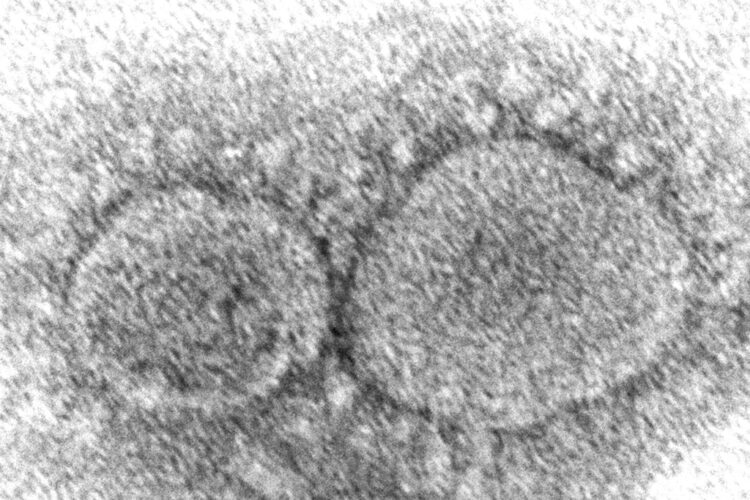

COVID-19